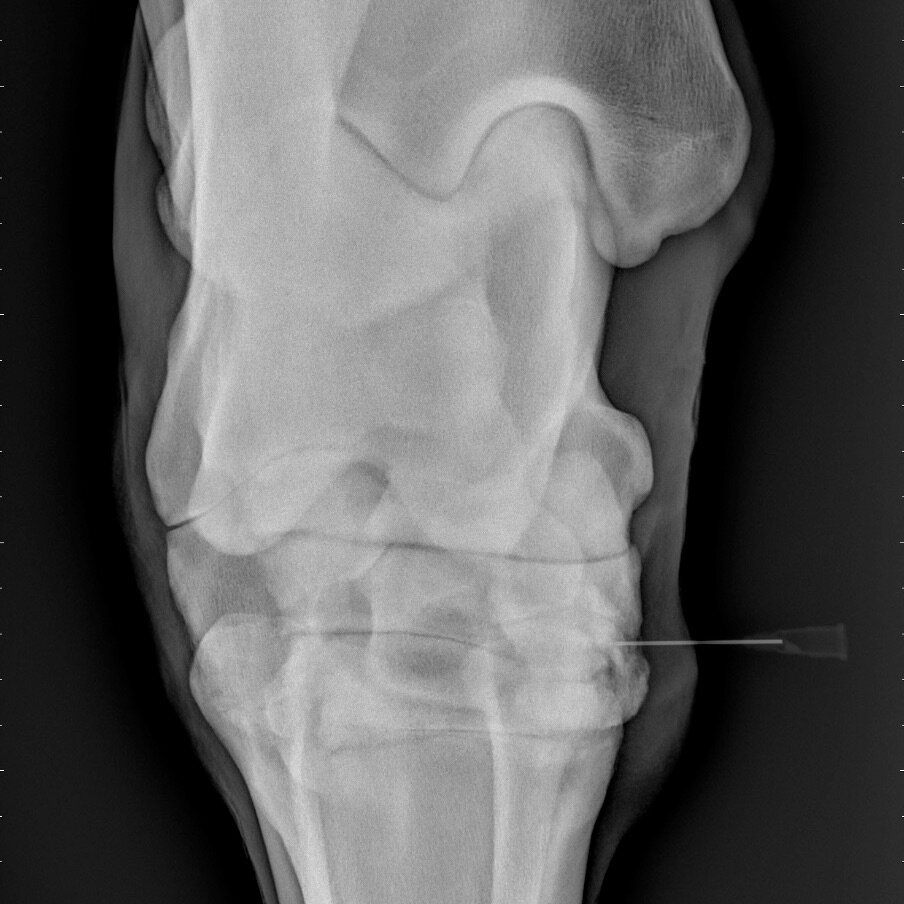

Management of joint disease often requires an injection in to the joint. The main product we use is a cortisone injection. People often ask me how often can they do this? And does this damage the joint?